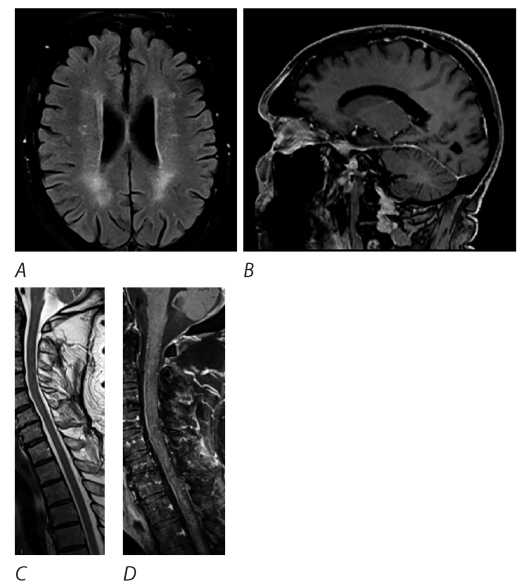

В течение следующего года состояние оставалось стабильным. Контрольное МРТ головного и спинного мозга (декабрь 2021 г.) продемонстрировало положительную динамику (рис. 2). МРТ головного мозга (апрель 2021 г.): без динамики.

Рис. 2. МРТ головного и спинного мозга пациента М. (декабрь 2021 г.).

А, С — T2-FLAIR/Т2-STIR: частичный регресс очаговых изменений в веществе головного и спинного мозга. В, D — Т1+С: отсутствие патологического накопления КВ в веществе головного мозга, уменьшение объёма и выраженности патологического контрастирования в веществе спинного мозга.

Fig. 2. Patient M.'s brain and spinal cord MRI (December 2021).

А, С — T2-FLAIR/Т2-STIR: partially resolved focal changes in the brain and spinal cord. В, D — Т1+С: no abnormal enhancement in the brain matter; decreased volume and intensity of abnormal enhancement in the spinal cord.